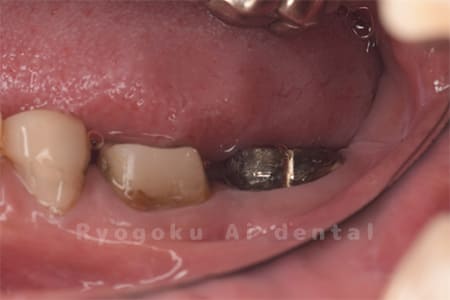

Case09

-

- 原因

- 左上6番重度カリエス

- 治療内容

- クラウンレングスニング

- 治療費用

- 44,000円(根管治療、補綴は別途費用)

他院で抜歯と判断された歯です。クラウンレングスニングを行い、保存を試みました。現在も問題なく被せ物が入り、使用できてます。

<リスク・副作用>

手術後は痛み、腫れ、痺れ、青あざなどの副作用が生じます。痛みは痛み止めを処方しますが、腫れ、青あざは1週間程度生じる場合があります。また、部位によっては神経の走行が複雑で、痺れが残り、長期的にお薬を処方する場合があります。